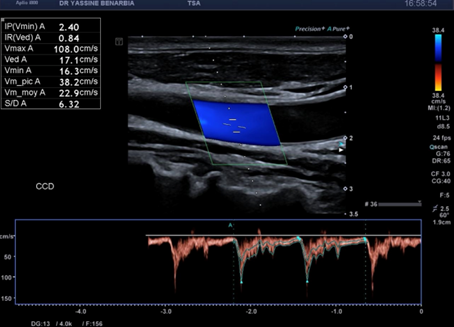

Cette dissection s'étend à la carotide commune droite proximale. Le Doppler pulsé dans le vrai chenal montre un spectre triphasique conservé avec une vélocité maximale de 108,0 cm/s (normale) et un index de résistivité de 0,84 confirmant l'absence de retentissement hémodynamique. L'artère sous-clavière droite et l’artère vertébrale restent perméables avec des flux normaux au doppler.

Les signes retrouvés à l'échographie-Doppler sont : flap intimal mobile visible en mode B séparant vrai et faux chenal, double lumière artérielle en coupe transversale et longitudinale, flux différenciés au Doppler couleur (vélocités élevées dans le vrai chenal, flux plus lent dans le faux chenal), et spectre Doppler pulsé conservé dans le vrai chenal (triphasique ou biphasique).

Les critères de stabilité à surveiller sont : taille du faux chenal inchangée, flux conservé dans le vrai chenal avec vélocimétrie normale (Vmax < 125 cm/s), absence d'extension de la dissection, absence de thrombose progressive, et absence de dilatation anévrysmale.